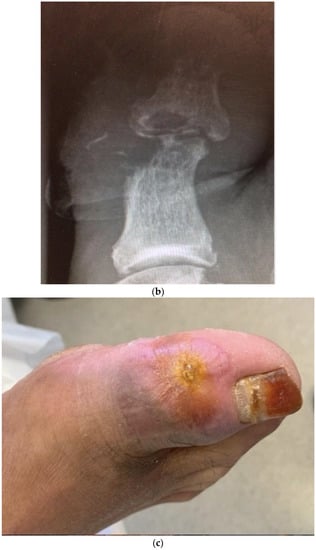

United Kingdom and United States—an early report on the effect of the pandemic on diabetic foot care from Manchester, United Kingdom and Los Angeles, USA compared and contrasted the approach and outcomes during the first lockdown period of March/April 2020 []. The threats to the management of DFUs during this difficult time are summarised in Table 3. It was during this first six-week lockdown that virtually all routine tests for outpatient services were suspended, emphasising the importance of good clinical medicine with careful history taking and, especially, examination of the feet. The inability to perform X-rays made clinical signs such as the “sausage toe” [] and the positive “probe-to-bone test” [,] very important as clinical markers for the presence of underlying osteomyelitis. The inability to do routine X-rays during this period of time led to the clinical decision alone being made to diagnose and treat osteomyelitis. Two cases from Manchester illustrate the importance of these signs. Figure 1 shows in this first case a large neuropathic wound on the medial side of the hallux which did probe-to-bone, suggesting osteomyelitis. As this patient was first seen in the week prior to lockdown, an X-ray was possible confirming the presence of osteomyelitis as shown in Figure 1b. The decision to treat with oral broad-spectrum antibiotics was made and Figure 1c shows the healed lesion some eight weeks later. This showed healing and a subsequent X-ray confirmed radiologic healing.

Figure 1.

Images from case 1. (a) Foot ulcer on medial side of right hallux prior to lockdown. (b) Radiograph of right hallux prior to lockdown showing extensive osteomyelitis and septic arthritis in both phalanges and interphalangeal joints. (c) Healed wound on right hallux after 8 weeks of antibiotics, 6 weeks post-lockdown. (Reproduced from [], with permission from ADA, 2020.)